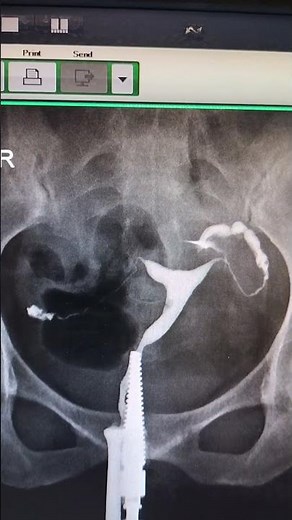

Hysterosalpingogram Procedure - HyCoSy

Procedure - Hysterosalpingogram